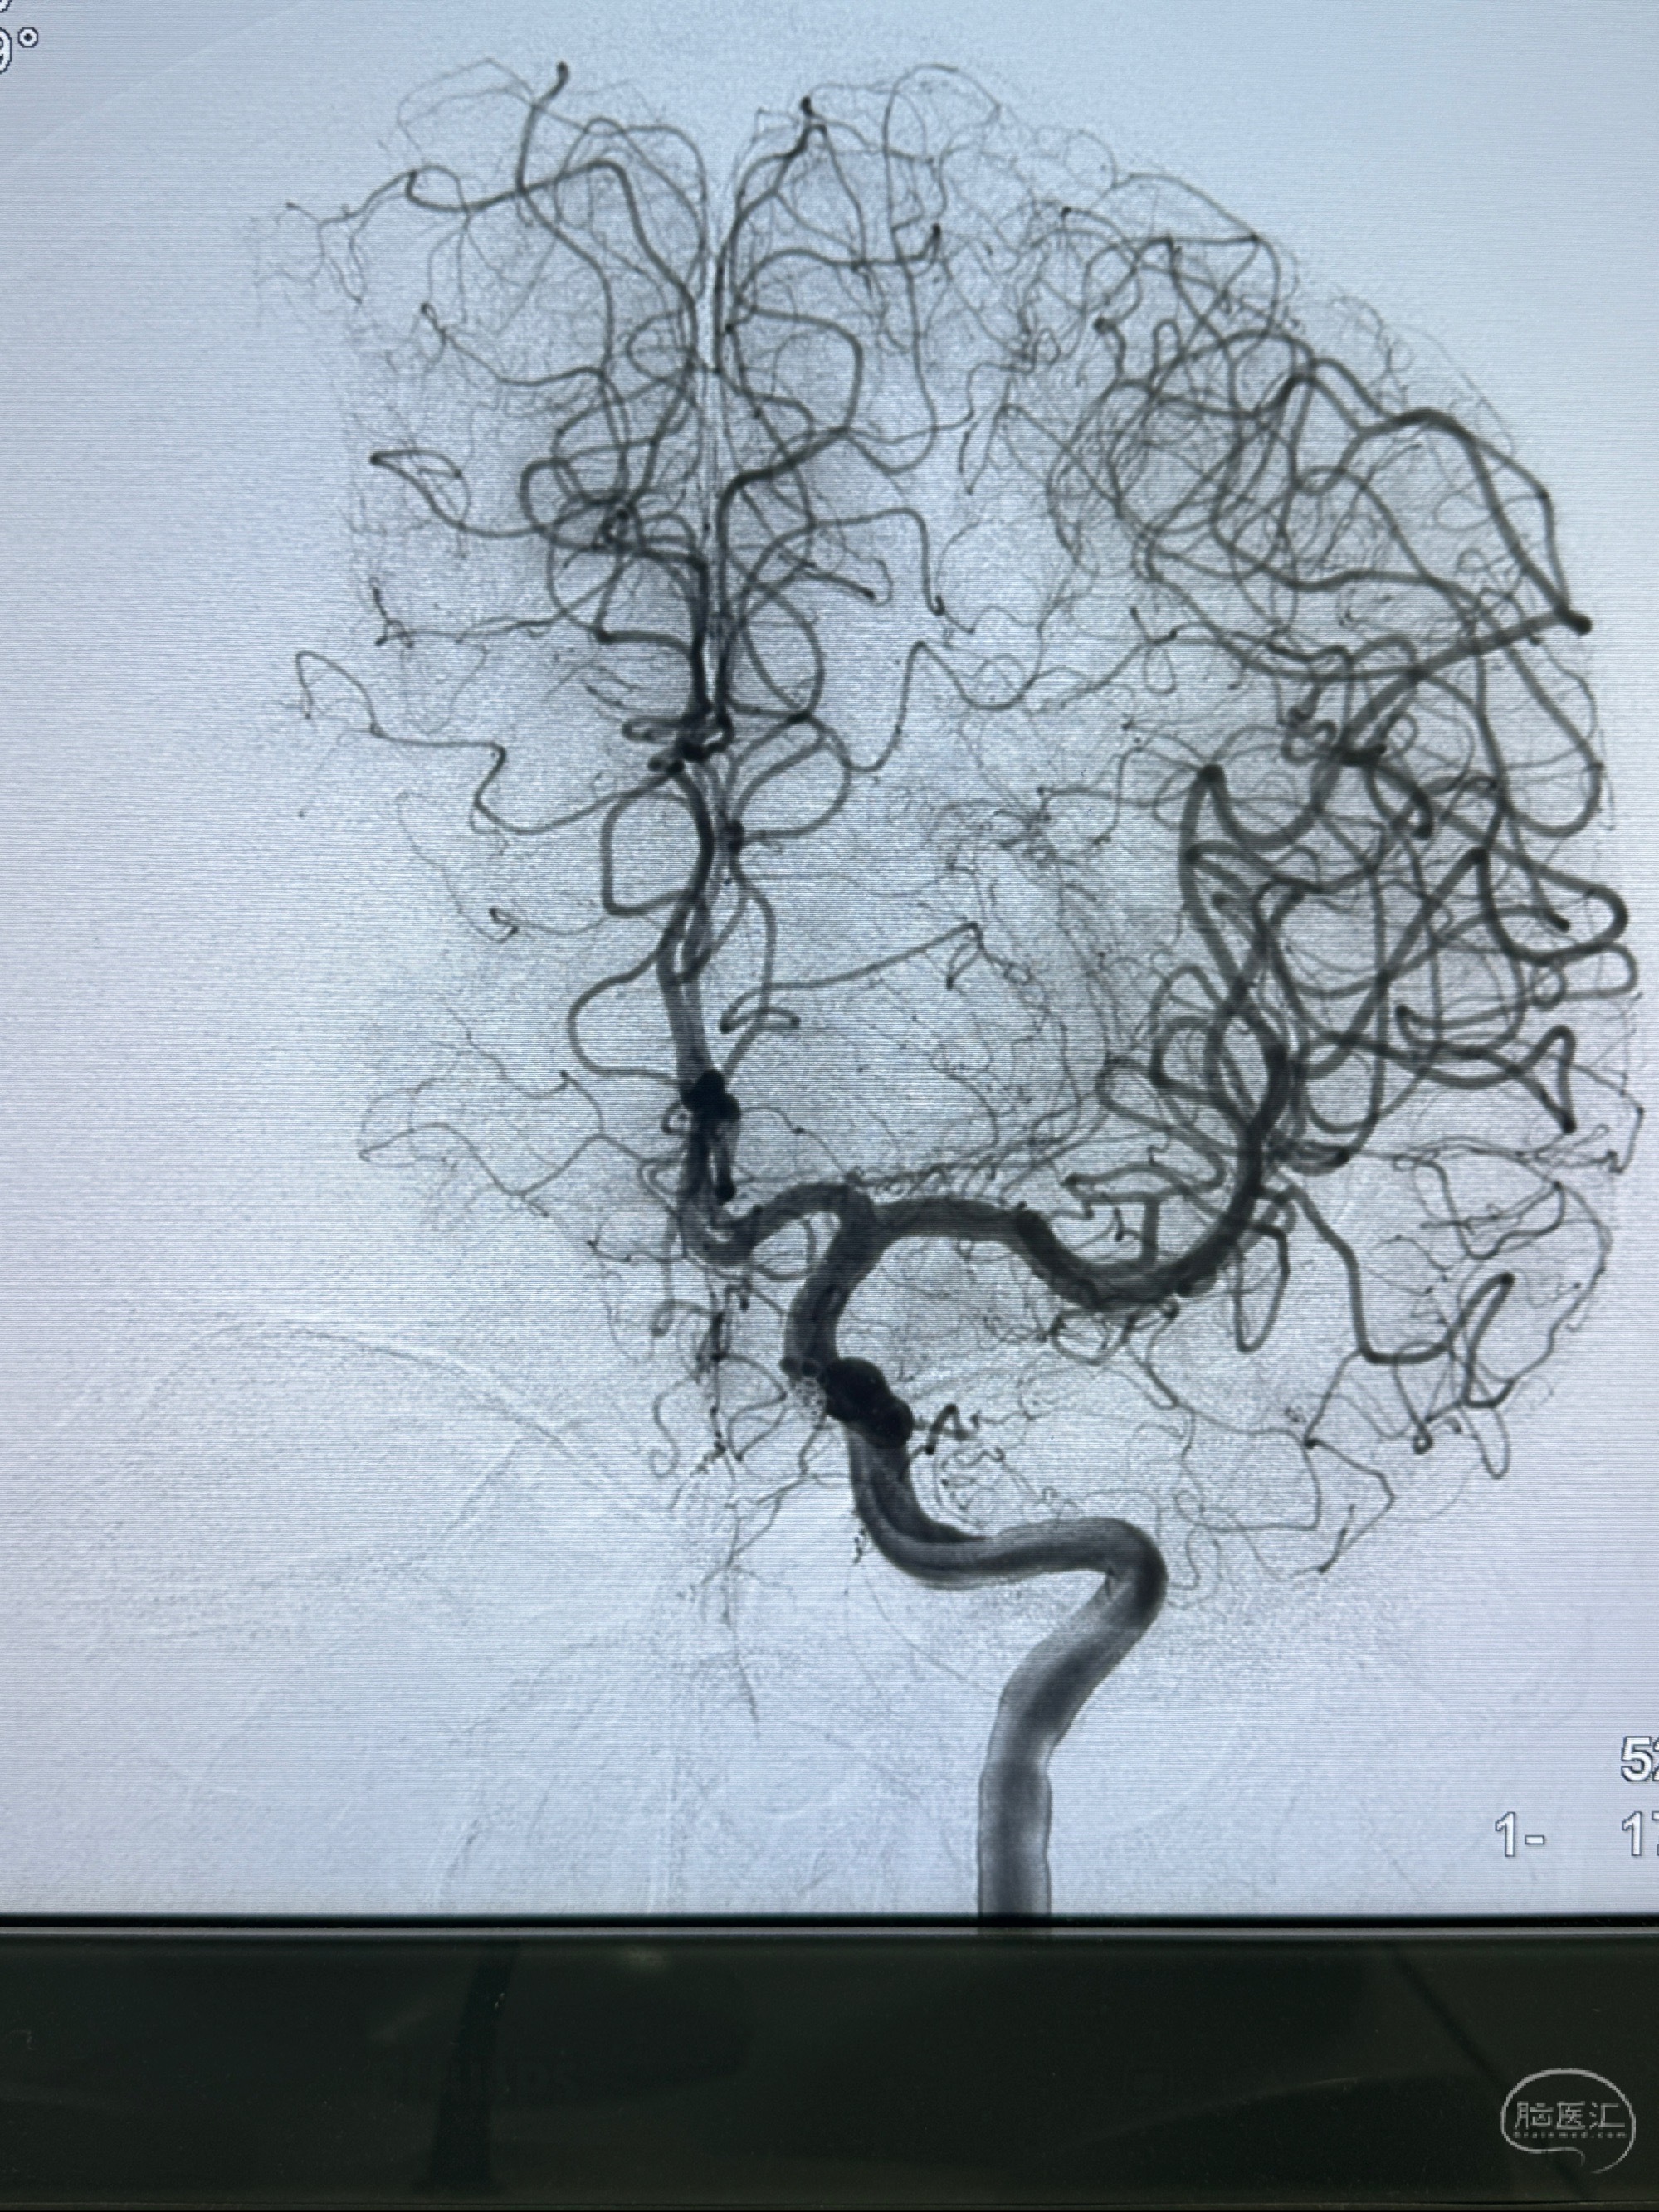

2023-11-13DSA:左侧颈内动脉眼动脉后壁动脉瘤

2023-11-29全麻下行NeuroformEZ4.5-20mm支架辅助栓塞